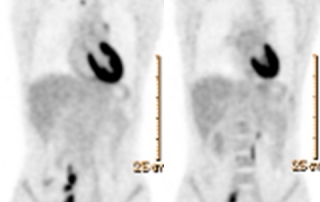

| Avant traitement | Après BEACOPP renforcé x 2 cycles Masse médiastinale dont le SUVmax est comparable au bruit de fond hépatique, correspondant à une réponse métabolique complète |

Résultat : la réponse métabolique complète après BEACOPP renforcé 2 cycles conduit à poursuivre le traitement par ABVD x 4 cycles selon l’essai AHL2011, avec évaluation après ABVD 2 cycles et en fin de traitement. La TEP-TDM montre une masse médiastinale résiduelle de taille 36 x 42 mm inchangée entre l’évaluation après 4 cycles et en fin de traitement, avec maintien de la réponse métabolique complète, correspondant à une diminution de 88%. Classement rémission complète incertaine selon les critères de Cheson 1999 et à une rémission complète selon les critères IWG 2007.